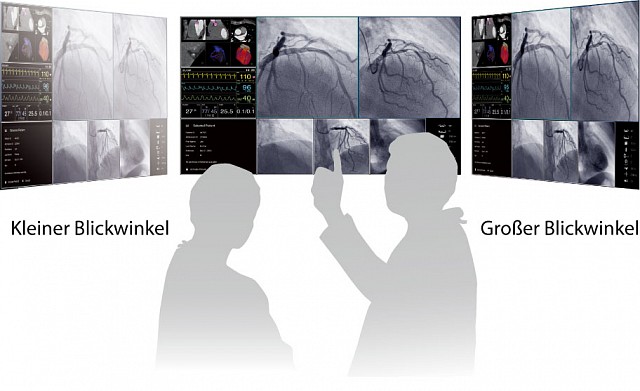

- Großer Blickwinkel durch IPS LCD Technologie.